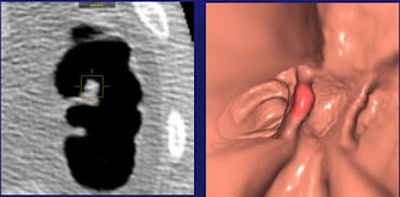

| Above, per-patient performance results segregated by bowel prep regimen show significantly improved sensitivity in individuals with 6- to 9-mm lesions who underwent fecal tagging. Below, combined results for detecting adenomas and hyperplastic polyps in all patients again demonstrate significant improvement only in individuals with 6- to 9-mm polyps. |